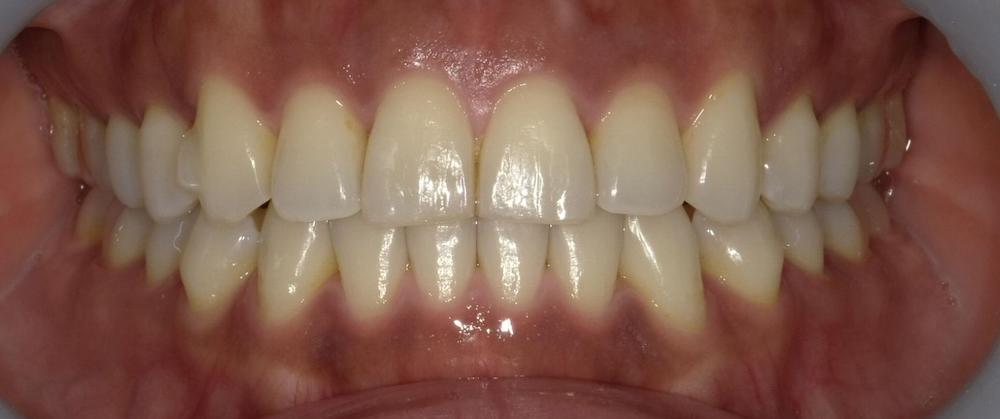

症例2 舌癖による後戻りケース (軽度)

舌を前歯に押し付ける癖があり、徐々に前に出てきてしまったため再矯正を行いました。矯正中から舌トレーニングを行い舌癖の改善に努めました。

- 治療方法 :インビザラインエクスプレス上下

- 治療期間 :6ヶ月

- 治療費用:¥385000(税込)

- 治療のリスク・デメリット :舌癖の改善をする必要がある

Before

After